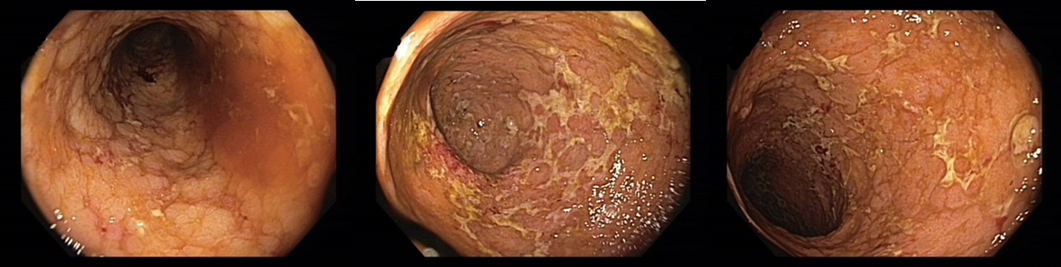

018/2 Slizniční zhojení. Monoterapie vedolizumabem

Slizniční zhojení

Histologie: lehká porucha architektoniky krypt, může se jednat o pozánětlivé změny. Jiné histopatologické změny přítomny nejsou.